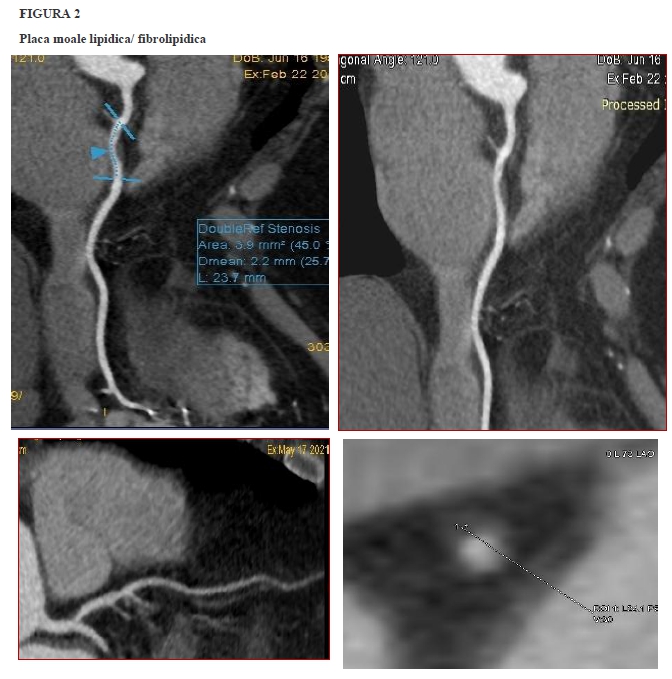

Sub acest auspiciu, conceptul de „placa vulnerabilă” a devenit relevant. Au fost identificate 4 prototipuri morfo-histologice asociate riscului înalt de declanșare a MACE. Plăcile aterosclerotice coronariene susceptibile la ruptură au morfologie distinctă, în comparație cu cele stabile. În linii mari, cele patru morfotipuri, stabilite ca atare prin corelație cu IVUS și cu aspectul histo-patologic, sunt descrise ca și:

■ placă voluminoasă cu structura predominant lipidică, localizată la limita intimă-medie a arterei, fără îngustare semnificativă a lumenului subiacent; asociază sau nu „dilatarea” arterei prin remodelarea pozitivă a peretelui,

■ depozit cu structură moale, predominant lipidică, dar delimitat prin lizereu („capișon”) fibros,

■ placă degradată în porțiunea centrală prin hemoragie/necroză (napkin-ring sign),

■ microcalcificări (spotty calcification) în placa lipidică/ fibrolipidică.

În cazul plăcilor vulnerabile, riscul de MACE nu se corelează fidel cu gradul stenozei, ci cu predispoziția la eroziune, ruptură, tromboză. De aici importanța identificării precoce a plăcii cu risc, iar singura metodă imagistică neinvazivă relevantă în evidențierea, caracterizarea și încadrarea morfo-structurală a plăcii vulnerabile este considerată, în prezent, angio-coronarografia CT.

Spre exemplificare, iată câteva imagini de coronarografie CT, în care sunt prezentate morfotopurile de plăci de aterom vulnerabile.